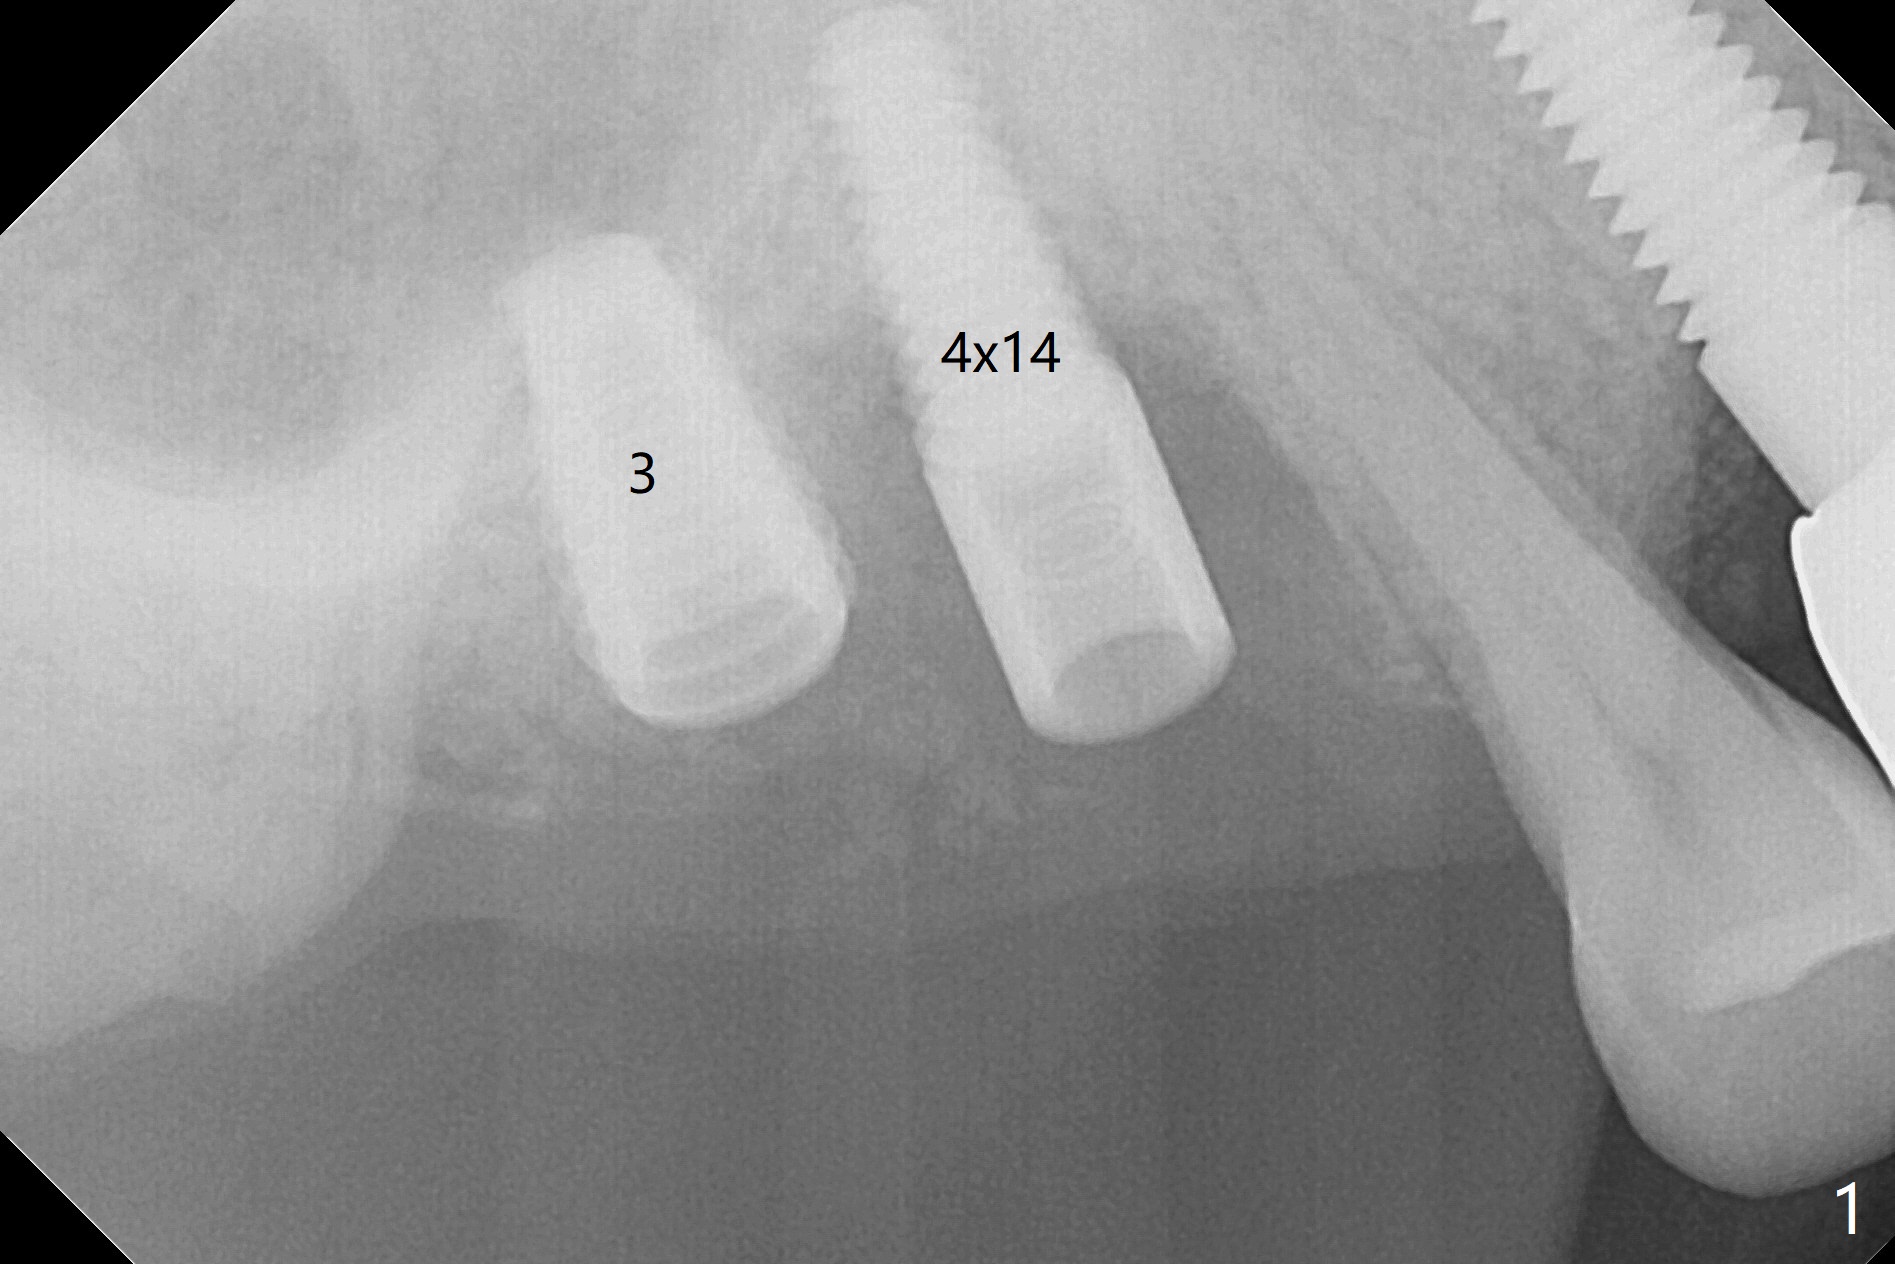

After osteotomy using bone-level implant guide at #4, the crown and abutment at #3 has to be removed to place a 4x14 mm tissue-level dummy implant because of the narrow space of #4 and implant placement angulation (Fig.1). Following initial placement of a final 4x17 mm implant and bone graft (Fig.2 *), the crown and abutment of #3 and the guide are reseated for correct implant trajectory. The guide has to be removed for final depth control. With the same mode, a 5x17 mm tissue-level tap is used at #2 following bone-level osteotomy with guide. A 5x14 mm tissue-level implant is placed with >50 Ncm (later placed deeper), while more bone graft is inserted mesial of #4 implant with a 3.5x5 mm abutment (Fig.3 *). Bone graft is introduced into the sinus using guided sinus lift kit (Fig.4,5 (CT sagittal and coronal sections)) * (D: distal, P: palatal)). The coronal half of the implant at #4 is covered by bone graft (Fig.6 *) buccal (B) and palatal within the deep socket. The implants at #2 and 4 seem to have osteointegrated nearly 5.5 months postop (Fig.7,8 (BW)). A 4.5x5 mm unipost is later placed at #2 with long chamfer margin. It appears that the abutment at #3 is wide. The hex is worn. It changes to a 5.5x7(4) mm one. After abutment adjustment for parallelism, a provisional FPD is fabricated. The latter will be adjusted for papilla formation between implants to reduce food impaction.